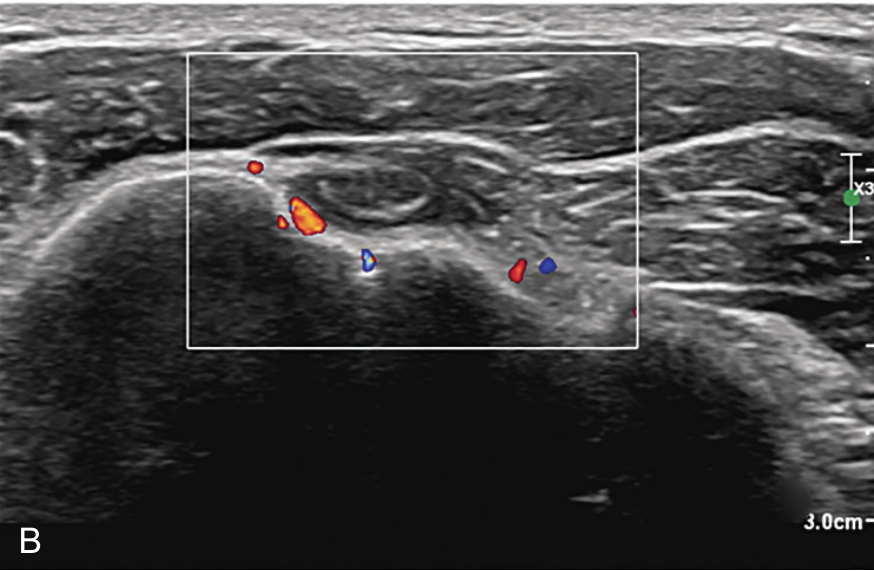

▲ 图2-3-4 超声引导下肱二头肌长头腱鞘介入治疗超声图(一)

A.二维超声:肱二头肌腱鞘内少量积液及滑膜增生;B.超声多普勒:肱二头肌腱鞘内及周围血流较丰富;C.平面内进针法,针尖进入肱二头肌长头腱鞘内;D注射治疗后腱鞘液体增多